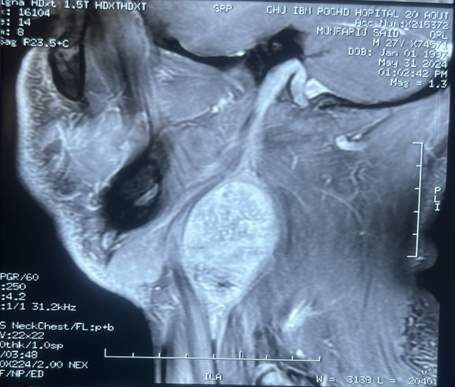

Magnetic resonance imaging (MRI)

of the neck confirmed a 39x38x60 mm properly limited mass with high signal

intensity on T1-weighted MRI and a heterogeneous, low signal intensity on T2

weighted MRI (Figure 1). After

intravenous administration of gadolinium-based contrast material, the lesion

showed irregular peripheral enhancement. Carotid artery angiography was

performed because of the close relationship between the mass and the carotid

artery. The angiography showed a normal filling in the right common, internal,

and external carotid arteries and their branches. (Figure 2).

Figure 2: Coronal (A) sagittal (B) and axial(C) view. Gray

arrow: well-circumscribed, h mass with dimensions of 39x38x60 mm in the right

lateral cervical region directly under the right sternocleidomastoid muscle,

separating the internal jugular vein and the carotid artery. Yellow arrow:

compressed internal jugular vein. Black arrow: carotid artery.